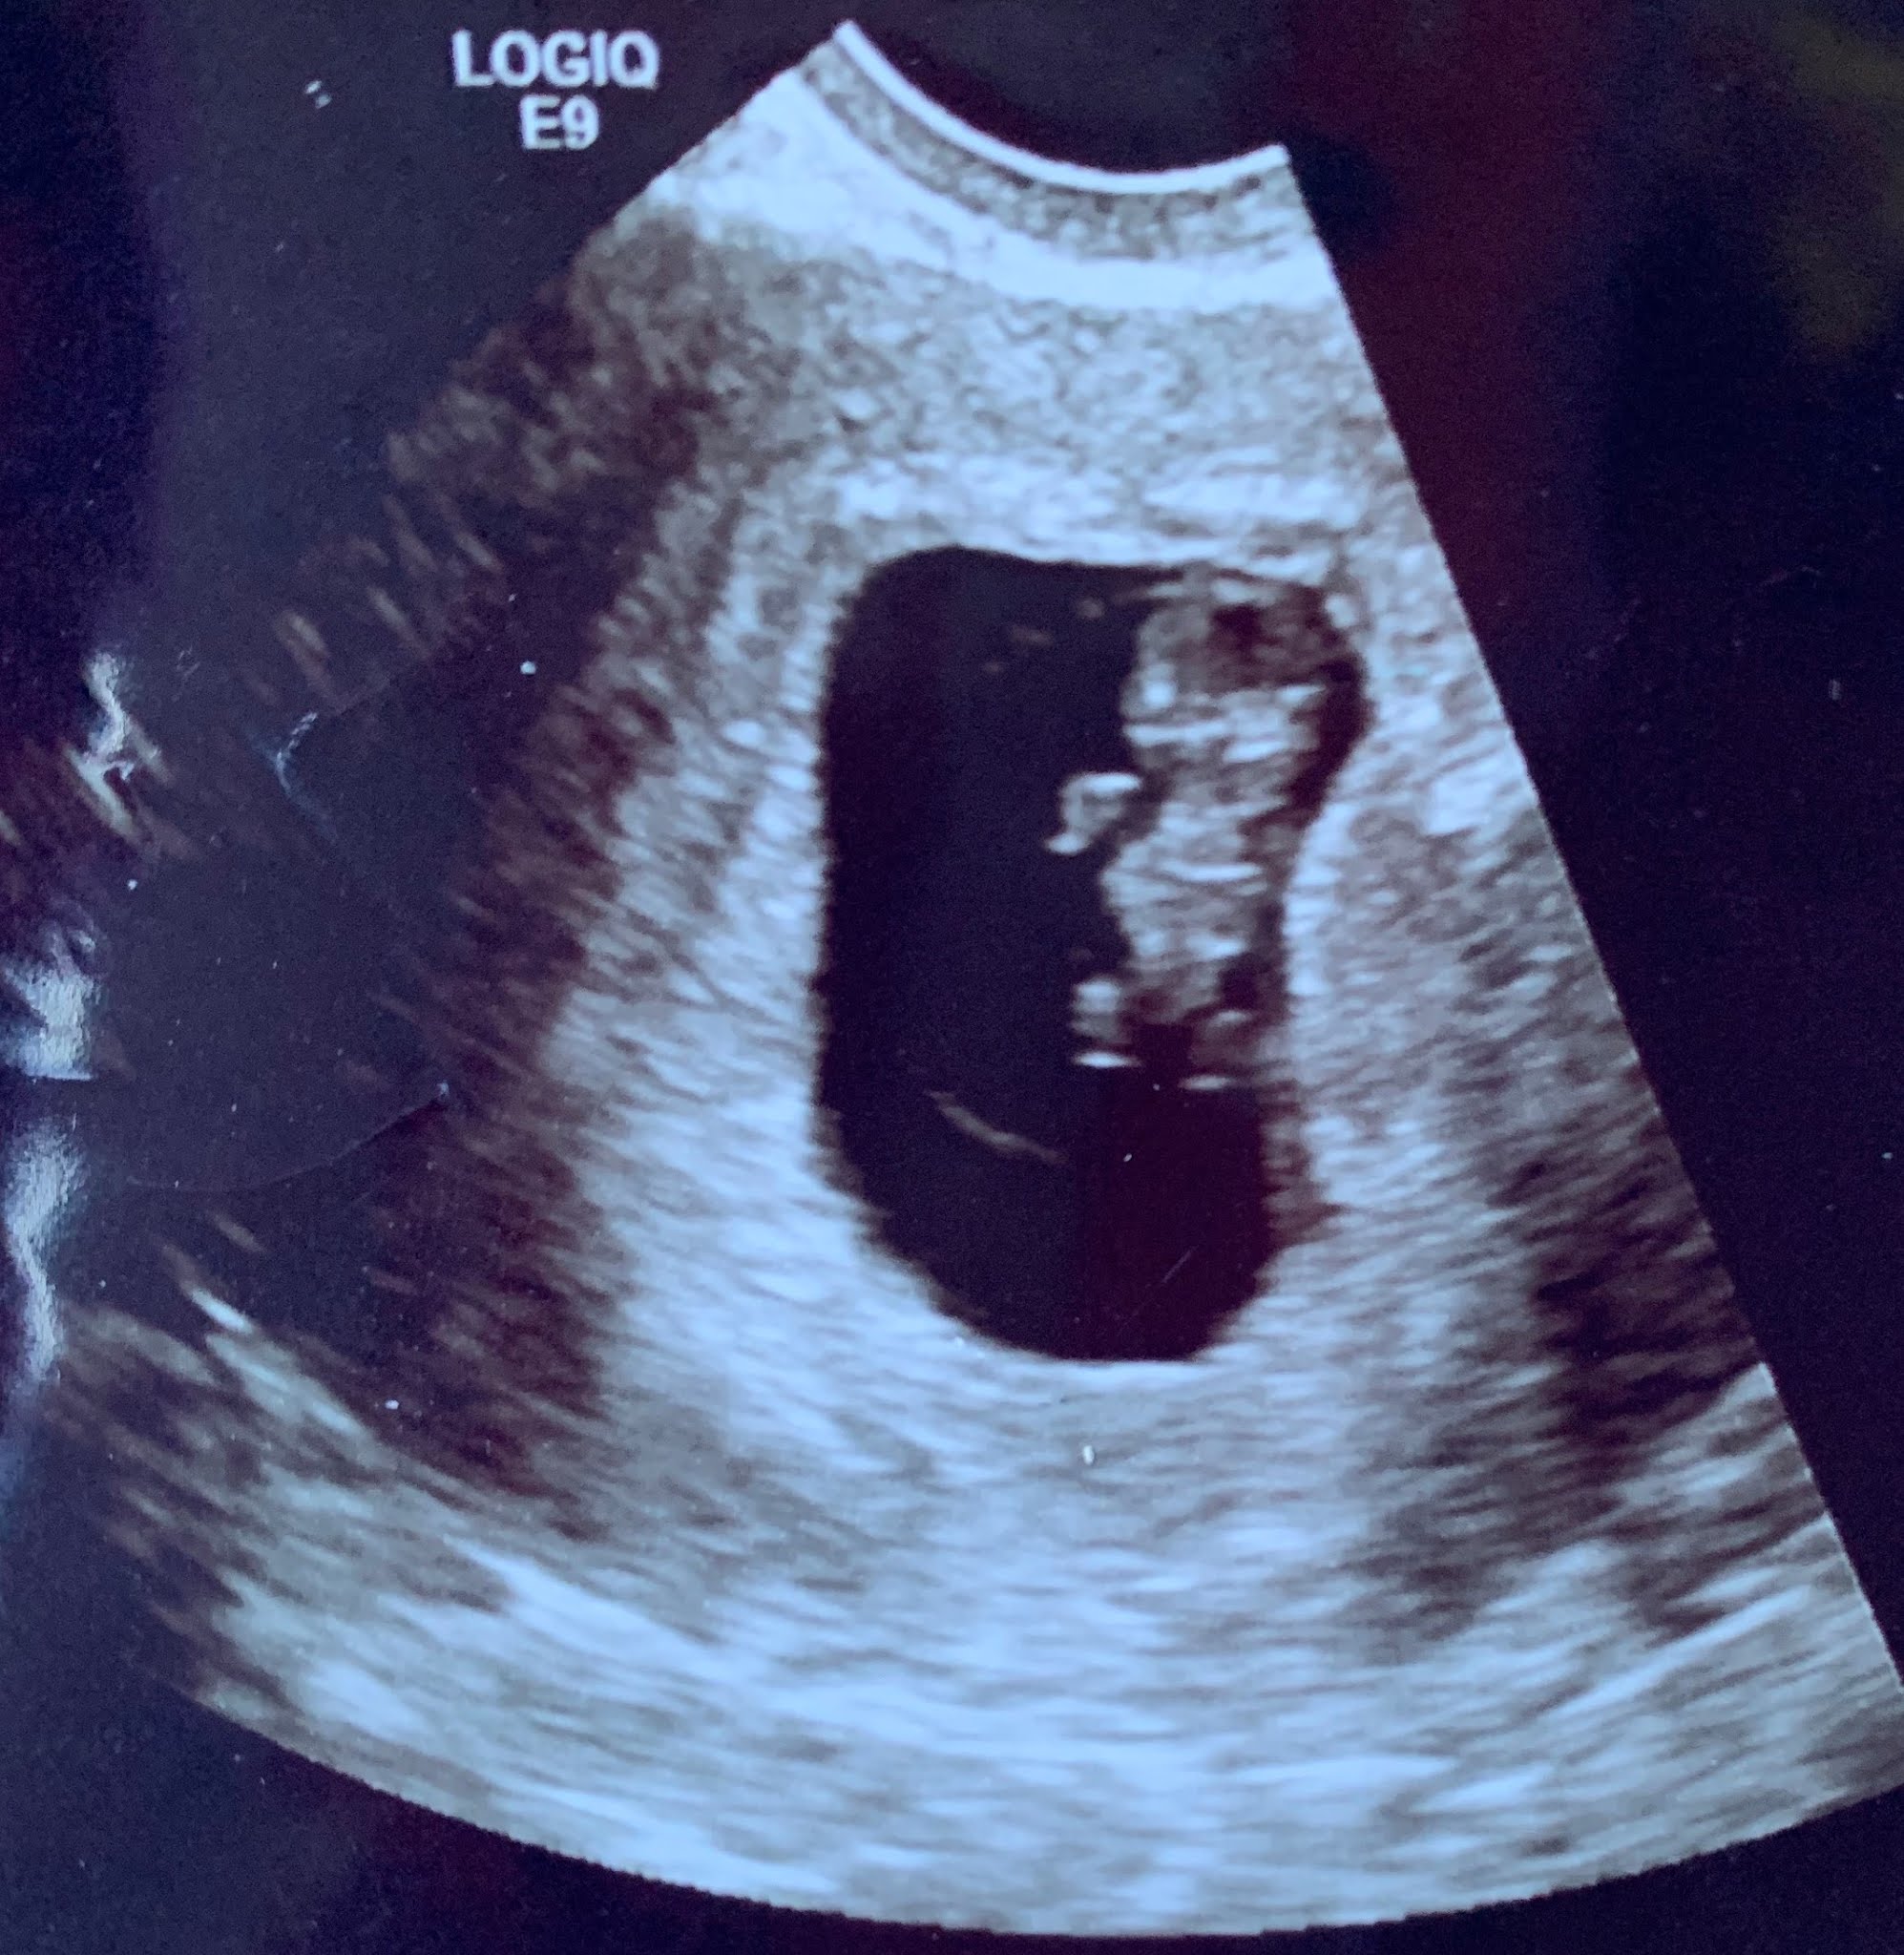

![]() |

| Ultrasound at 7 weeks, 2 days |